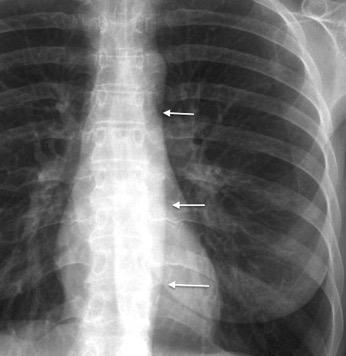

62. LÍNEAS PARAESPINALES. DESPLAZAMIENTO BILATERAL DE

Mieloma múltiple

Ganglios. (LLC, linfoma)

Osteofitos/ Lipomatosis

Fibrosis

Espondilodiscitis

Tb, Brucella, Cocos,

Inespecífica

Hematoma mediastínico

Hematopoyesis

extramedular

Meningoceles

Sistema ácigos dilatado

Tumor neurogénico

Fracturas vertebrales

Lipomatosis.